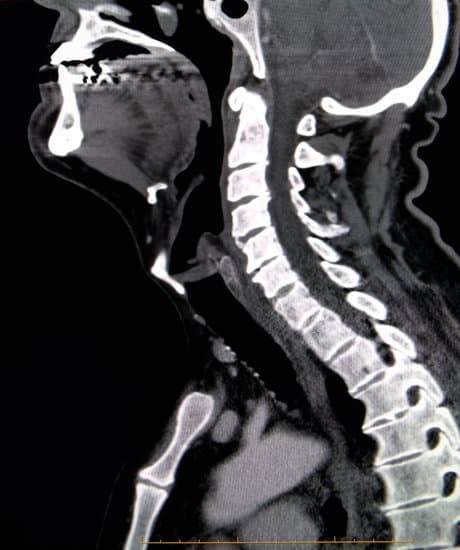

경추 디스크 CT (컴퓨터 단층촬영): 필요성과 검사 방법

CT(컴퓨터 단층촬영)는 여러 각도에서 촬영된 X-ray 영상을 조합해 신체 내부의 단면을 정밀하게 보여주는 검사입니다.

특히 경추 디스크와 골 구조를 세밀하게 평가하는 데 유용합니다.

CT는 경추 부위의 뼈 손상과 함께 디스크와 관련된 문제를 일부 확인할 수 있어, 특정 상황에서 MRI와 보완적으로 사용됩니다.

CT에서 확인할 수 있는 경추 디스크 소견

골절 및 탈구

경추의 급성 외상 후 골절 여부를 정밀하게 진단합니다.

퇴행성 변화

뼈 사이에 생긴 **골극(뼈 돌기)**과 같은 퇴행성 변화를 확인할 수 있습니다.

디스크 돌출 및 탈출

디스크가 돌출되어 척추 신경을 압박하는지 평가합니다.

MRI와 비교해 골성 병변과 연관된 디스크 문제를 명확히 볼 수 있습니다.

척추관 협착증

디스크와 골격의 변형으로 인해 척추관이 좁아지는 상태를 확인합니다.

이로 인해 발생하는 신경 압박을 평가합니다.

CT(컴퓨터 단층촬영)는 경추의 골격 구조와 외상 평가에 유용한 검사입니다.

디스크와 신경 문제는 주로 MRI로 확인하지만, CT는 골절이나 퇴행성 변화와 같은 골성 병변을 명확하게 보여줍니다.

특히, 급성 외상이나 MRI 검사가 어려운 경우 CT가 중요한 대체 수단으로 활용됩니다.

정확한 진단을 위해 상황에 따라 MRI와 CT를 병행할 수 있습니다.